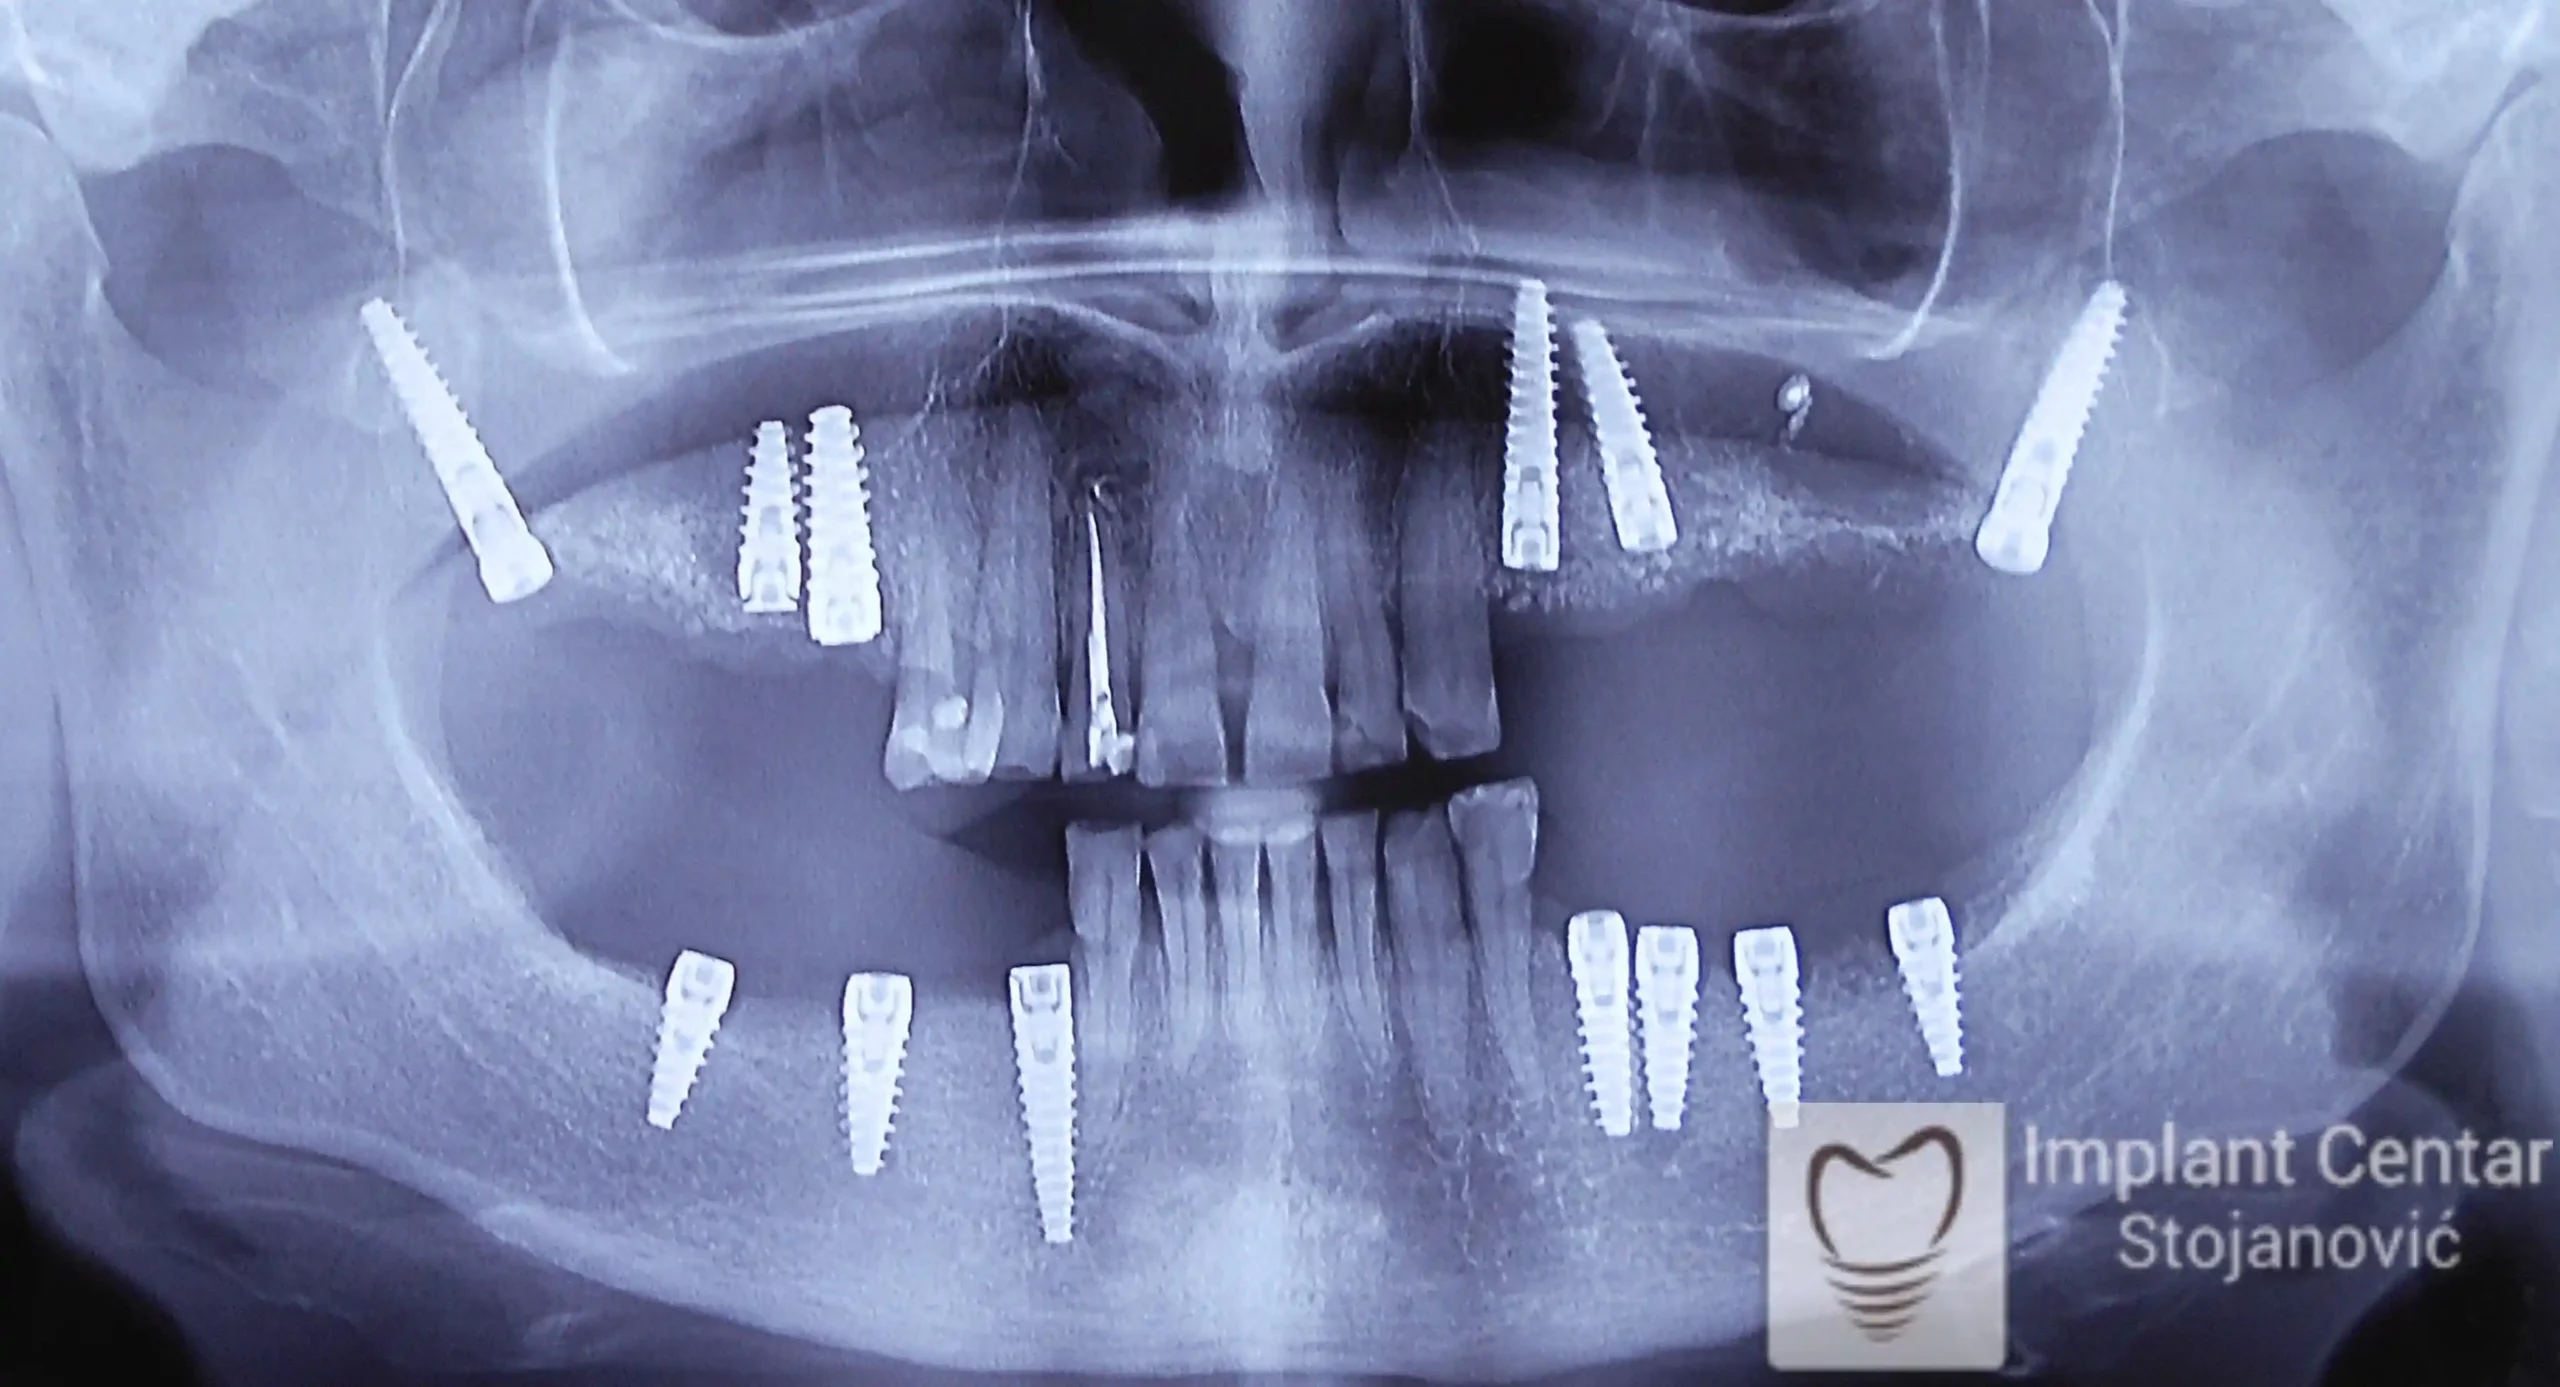

Zbog toga je plan terapije uključivao vađenje svih preostalih zuba i ugradnju implantata u gornjoj i donjoj vilici. U gornjoj vilici postavljena su i dva tuberopterigoidna implantata, kao zamena za sinus lift proceduru, što se može videti na ortopan snimku nurađenom odmah nakon ugradnje (slika 3).

Već tri dana nakon operacije, pacijent je zbrinut fiksnim privremenim zubima na implantatima, čime je odmah povraćena funkcija i estetika osmeha.

Nakon završetka perioda integracije implantata, izrađeni su cirkonijum-keramički mostovi u gornjoj i donjoj vilici (slika 6.).